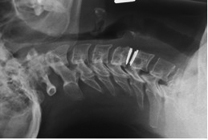

- In allen anderen Fällen wird durch einen kleinen Hautschnitt von 2-3 cm der Wirbelkanal dargestellt.

- Unter dem Operationsmikroskop wird der Nerv weggehalten und das herausgesprengte Bandscheibenmaterial entfernt.